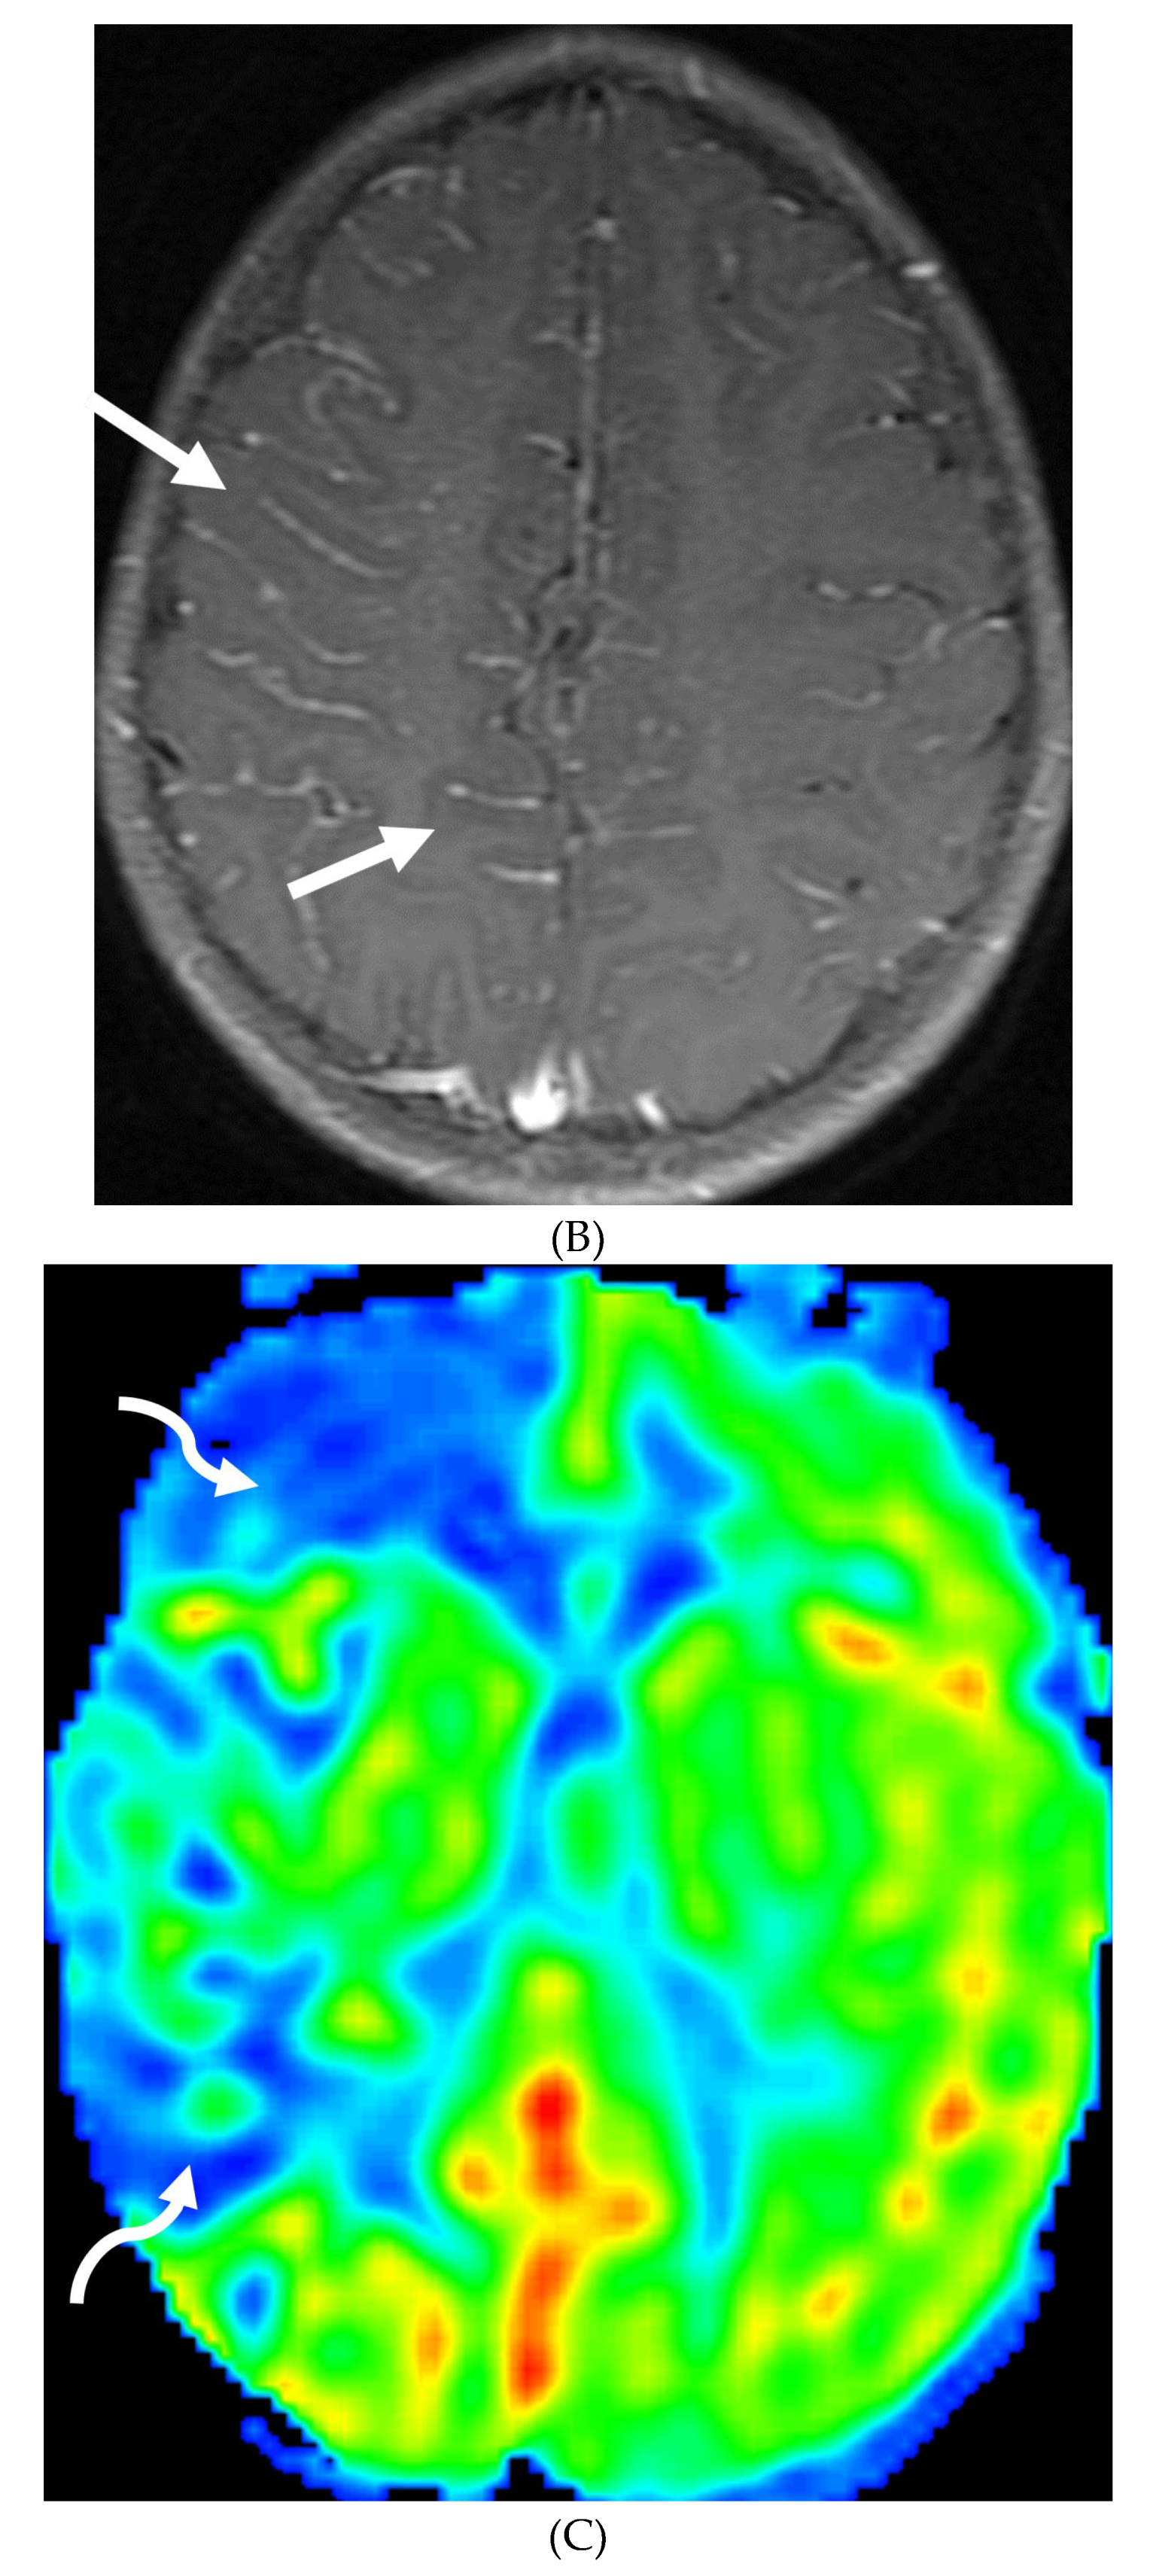

POSTERIOR REVERSIBLE ENCEPHALOPATHY SYNDROME (PRES)